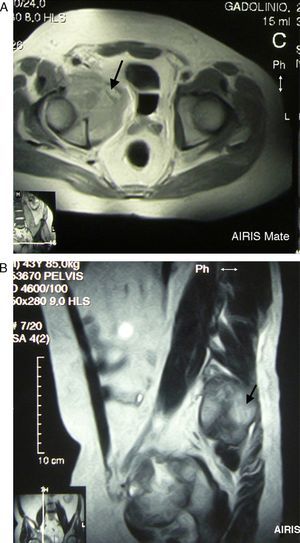

A 43-year-old male came to the clinic due to mechanical lower back pain, which had lasted for 2years. Physical examination showed painful limitation for right leg flexion and extension, with no neurological deficit. Laboratory analysis highlighted hemoglobin 10.6g/dl, normal ESR and GGT 111U/L (0–40). Simple X-ray (Fig. 1), CT (Fig. 2) and MR (Fig. 3) of the hips evidenced a 90mm×80mm×80mm mass in the right hemipelvis with an osteolytic component which affected half of the cotillus, iliac and pubic ramus, displacing the bladder and subjacent structures leftward.

(A and B) Axial and coronal MR of the hips RM in T2 sequence with contrast. A voluminous mass in the right hemipelvis is shown, affecting the anterior half of the cotillum, the iliac and pubic ramus, displacing the urinary bladder and adjacent structures leftward, with an isointense signal with bone and increased intensity with contrast, except in areas of intense necrosis.